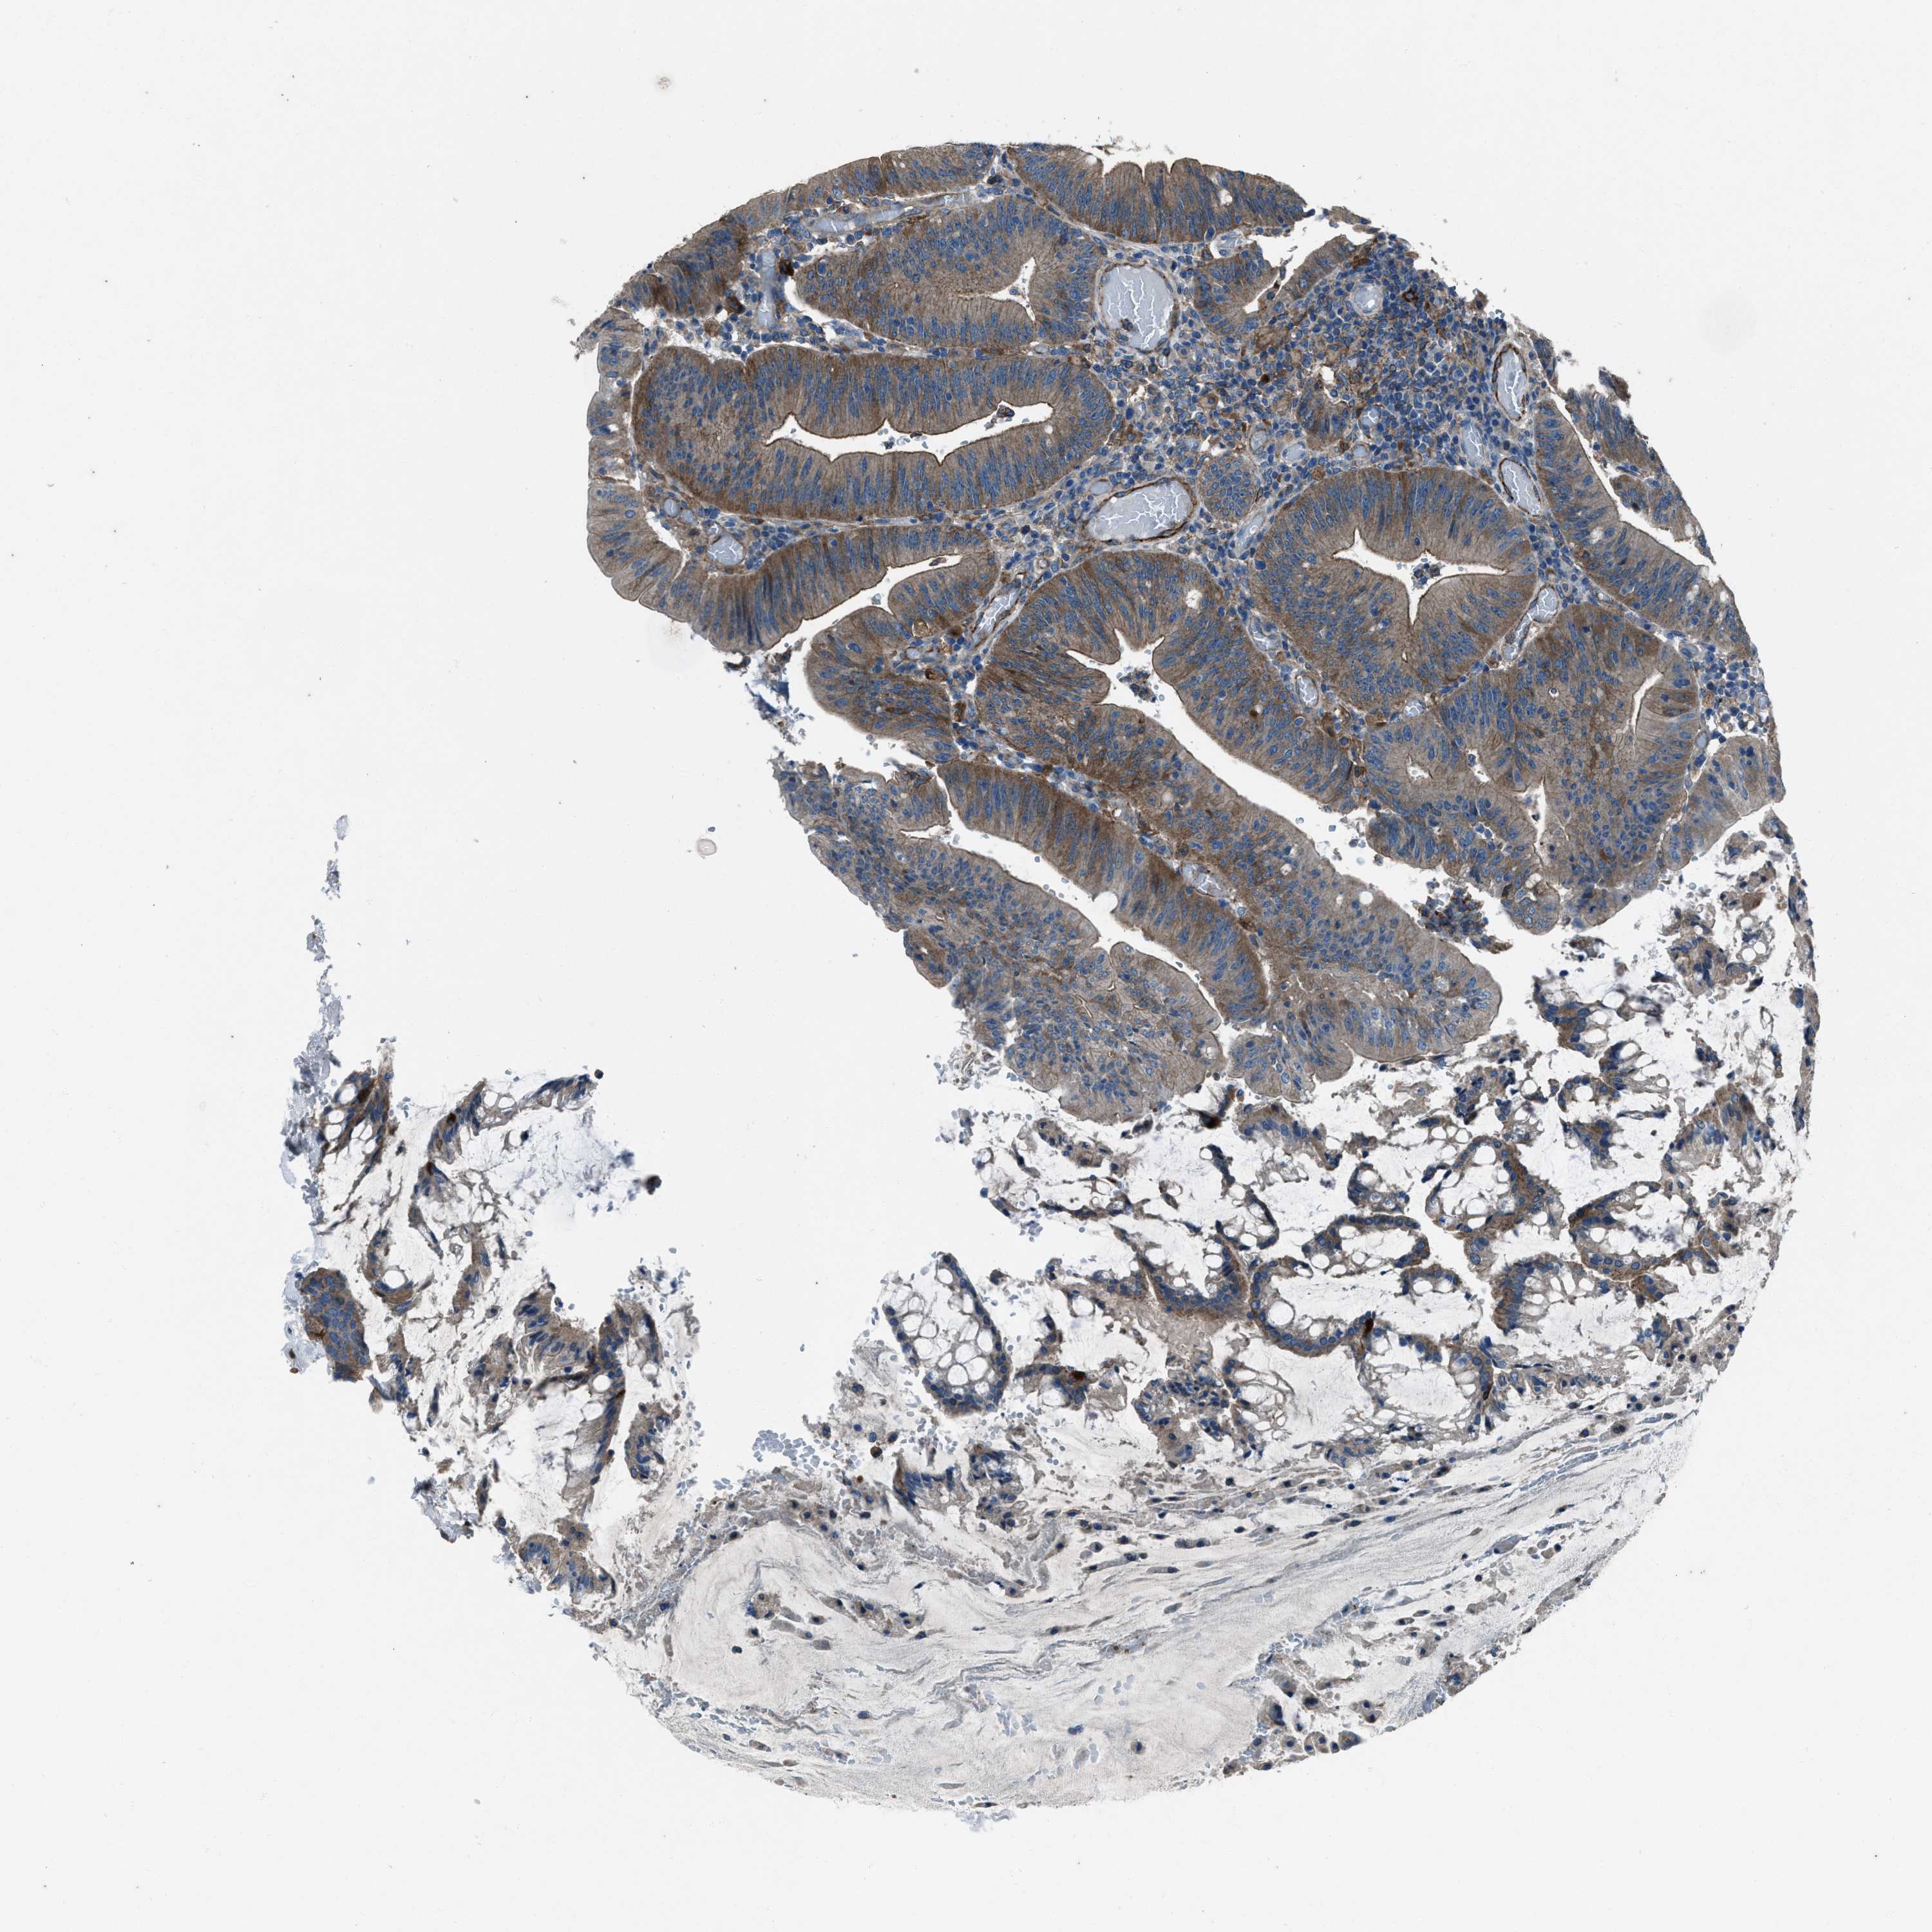

CANCER COLORECTAL CANCER Show tissue menu

Colorectal cancer

Human cancer

Colon adenocarcinoma

Rectum adenocarcinoma